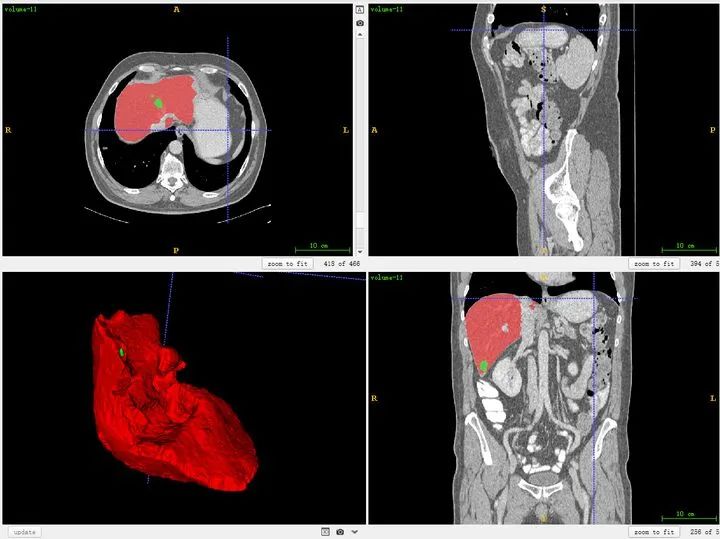

ITK-SNAP is a visualization tool for intuitively inspecting 3D medical image structures and can also be used for segmentation and bounding-box annotation. It is free and widely used. The ITK-SNAP official download page is available. Mango is another lightweight visualization tool that can be tried. I generally use ITK-SNAP.

It is important to clarify anatomical directions. The three viewer panes correspond to three orthogonal planes, indexed as shown below. For example, the upper-left pane corresponds to the R-A-L-P orientation, which is the plane viewed from feet to head (the z direction).

You can also load segmentation results to compare against images.